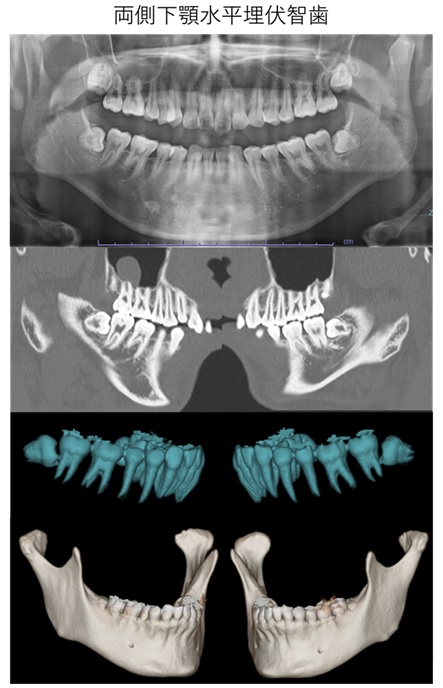

埋伏歯の抜歯

埋伏歯とは、歯茎や顎の骨の中に埋まって出てこない歯のことを指します。特に親知らず(第三大臼歯)が埋伏することが多く、通常17歳から25歳頃に生えてくる最後の歯です。多くの場合、親知らずは正しい位置に生えず、周囲の歯や歯茎に問題を引き起こすことがあります。

抜歯は、局所麻酔を用いて痛みを感じないように行います。埋伏歯の抜歯が複雑である場合や、患者さんが不安を感じる場合には全身麻酔を使用します。